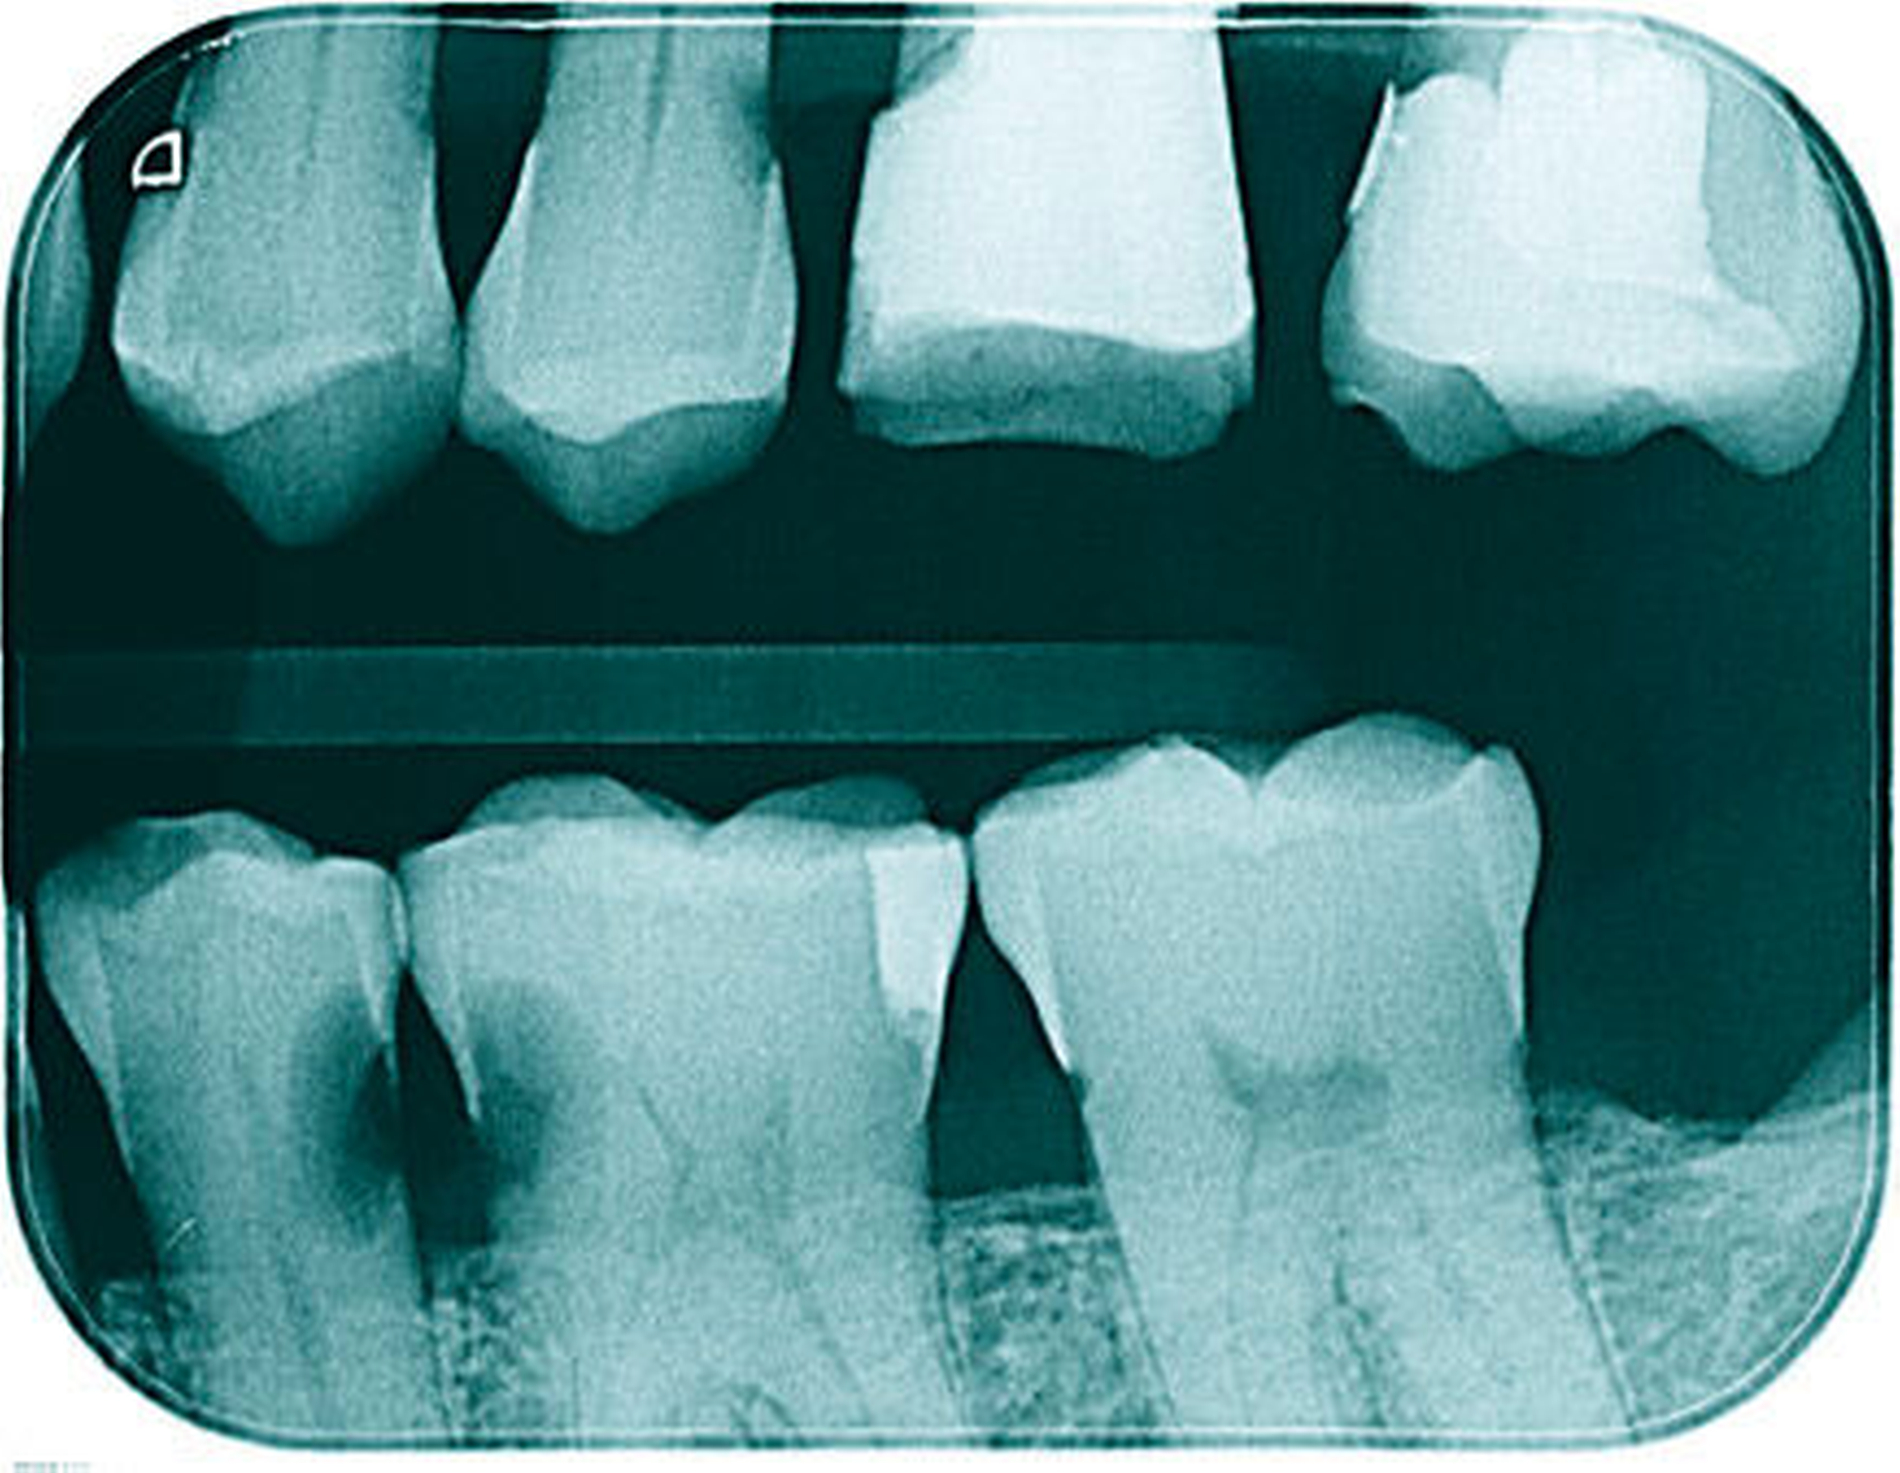

In der aktuellen Deutschen Mundgesundheitsstudie (DMS V) konnte gezeigt werden, dass insbesondere Zähne von pflegebedürftigen Senioren häufig Wurzelkaries aufweisen. Da Wurzelkariesläsionen in unzugänglichen Bereichen wie Approximalräumen schwer zu therapieren sind (Abbildung 2) und die Therapieoptionen bei pflegebedürftigen Patienten meist eingeschränkt sind, ist es von großer Bedeutung, der Entstehung von Wurzelkaries bei Senioren vorzubeugen.